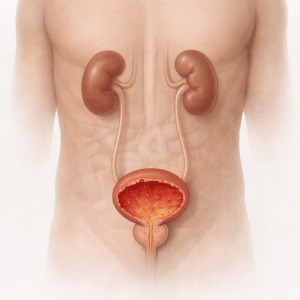

Bladder & Urinary Infections

What Are Bladder & Urinary Infections? Bladder infections and urinary…

Urinary Incontinence

What is Urinary Incontinence? Urinary incontinence is the unintentional loss…

How to Get Rid of a Bladder Infection: Guaranteed Results

Imagine the relentless pain of a bladder infection, trips to the bathroom,…

Best Antibiotics for UTIs: Symptoms, Treatment & Prevention

UTIs have the potential to hit you like a ton of bricks,…

Bladder Health Check: Understanding Urinary Incontinence

How Fast Can You Get Rid of a Bladder Infection?

Best Antibiotics for UTIs: Test Your Knowledge